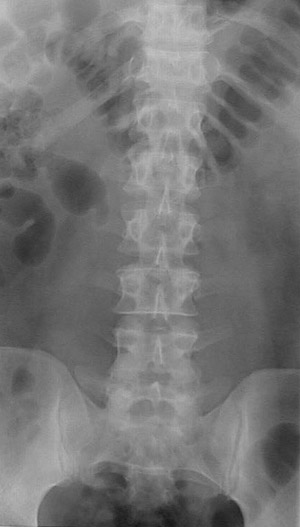

This is a normal AP radiograph of the lumbar spine demonstrating the 12th rib and L1 spinous process and L3 pedicle and L2-L3 apophyseal joint and L4 transverse process and intervertebral disc and sacrum and sacroiliac joint and iliac crest.